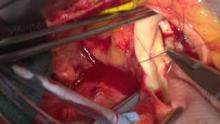

1. After the heart was arrested, a partial transverse aortotomy was made 1.5 cm above the sinotubular junction, stopping right above the left-non commissure post.

2. The scarred aortic valve was excised and the annulus was debrided. The annulus was sized to be 19 mm.

3. The left-non commissure post was incised from the aortotomy into the aorto-mitral curtain.

4. The incision was extended in a “Y” fashion undermining the left and noncoronary annulus to their respective nadir, but not reaching the muscular portion on the left or the membranous septum on the right. The tissue underneath the nadirs, the left and right fibrous trigone, is strong fibrous tissue. We use that tissue to anchor the patch.

5. A rectangular shaped Hemashield Dacron patch was trimmed in width slightly longer than the distance between the two cusp nadirs. This patch was sewn to the aorto-mitral curtain/mitral annulus from left to right fibrous trigone with running 4-0 Prolene suture. The suture line was transitioned to the undermined aortic annulus at the nadir of both left and noncoronary sinuses, sutured along the longitudinal length of the patch up to the level of the transverse aortotomy incision and secured.

6. The upsized Magna Ease valve sizer was placed in the enlarged root touching three nadirs of the aortic annulus and the position of the sizer on the patch was marked to guide the placement of valve sutures.

7. The non-pledgetted 2-0 Ethibond sutures were placed along the native aortic annulus in a noneverting fashion started from the right coronary sinus side and from outside in on the patch.

8. The bioprosthesis was placed with one strut facing the left-right commissural post, and all the valve stitches were passed through the sewing ring.

9. The sutures at nadirs of noncoronary and left coronary sinuses, which were the lowest points of the aortic annulus, were tied first to seat the valve well and prevent paravalvular leak. A portion of the patch lay beneath the prosthetic valve thereby enlarging the root and left ventricular outflow tract.

10. The aortotomy was then closed first by sewing the aorta to the left side of the patch almost to the mid part of the aortotomy, then from the pulmonary artery side to close the native aorta to aorta and tie to the suture closing the left side of the patch. The patch was trimmed and the right side of the patch and aorta was closed.